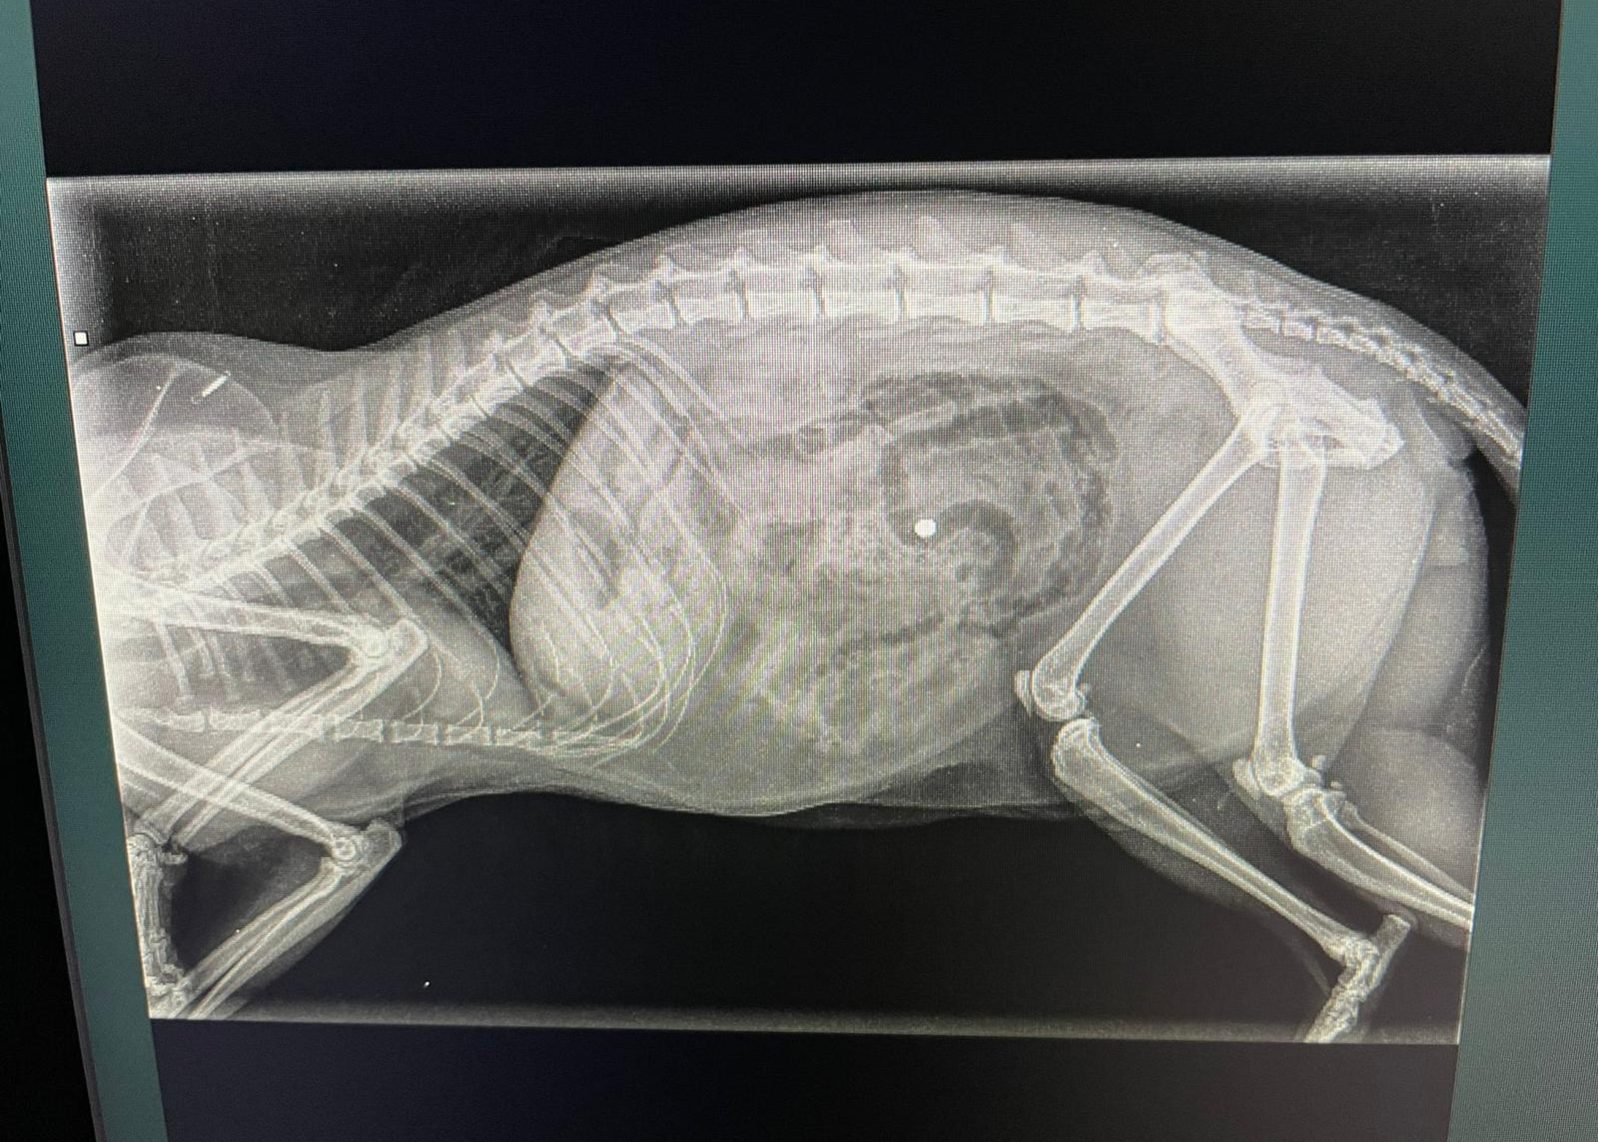

Artrose bij honden en katten Bij Dierengezondheidscentrum Weemelanden-Twenterand streven we naar de beste zorg voor uw trouwe viervoeters. Een veelvoorkomende aandoening die wij tegenkomen bij zowel honden als katten is artrose, een gewrichtsaandoening die kan leiden tot pijn en verminderde mobiliteit. Wat is Artrose? Artrose, ook bekend als osteoartritis, is een progressieve aandoening waarbij het…